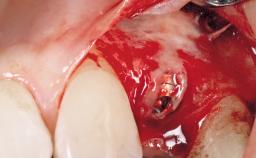

Late Placement of an Implant in a Maxillary Left Central Incisor Site

A 30-year-old female patient had lost tooth 21 and was referred to our clinic for consultation and treatment. Due to advanced apical infection, tooth 21 had been extracted two months earlier at another clinic and an acrylic-resin tooth had been bonded to the adjacent teeth. The patient desired implant treatment to avoid any damage to the adjacent natural teeth. While the patient had no history of any systemic disorder, she was a heavy smoker and exhibited medium to advanced periodontitis in the entire jaw. After the initial treatment to achieve a pocket probing depth of less than 4 mm and no bleeding on probing, a decrease in the height of the papillae mesial and distal to the extraction site and overall gingival recession were observed.

Bone Augmentation Horizontal|Staged

Augmentation Materials Autogenous chips|Membrane

Soft Tissue Grafting Simultaneous

Bone Volume Deficient horizontally, requiring prior grafting